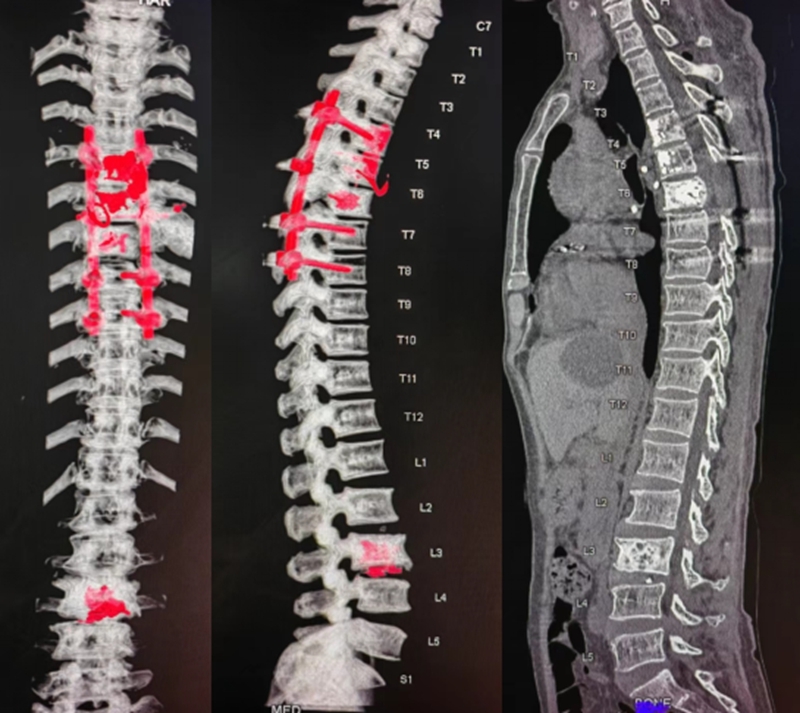

随后,骨肿瘤团队为患者做了肿瘤分离手术,切除了压迫脊髓的肿瘤,胸椎4、5、6椎体转移病灶射频消融骨水泥填充并用椎弓根螺钉将脊柱固定,第3腰椎椎体转移病灶射频消融骨水泥填充术。术后恢复情况良好,背部疼痛症状也已迅速缓解,术后第二天,瘫痪的肌肉也逐步有了恢复收缩活动,而且术后患者胃口大开,精神状态好。患者历经5年多的抗癌治疗后继发了脊柱转移致瘫痪,万念俱灰后,她重新感受到了下肢恢复的感觉和肌肉力量,现已顺利出院。

图1c 胸椎6椎板减压、肿瘤切除、胸椎4-6椎体病灶射频消融骨水泥填充、椎弓根螺钉固定,L3椎体转移病灶射频消融骨水泥填充术,术后CT重建所见